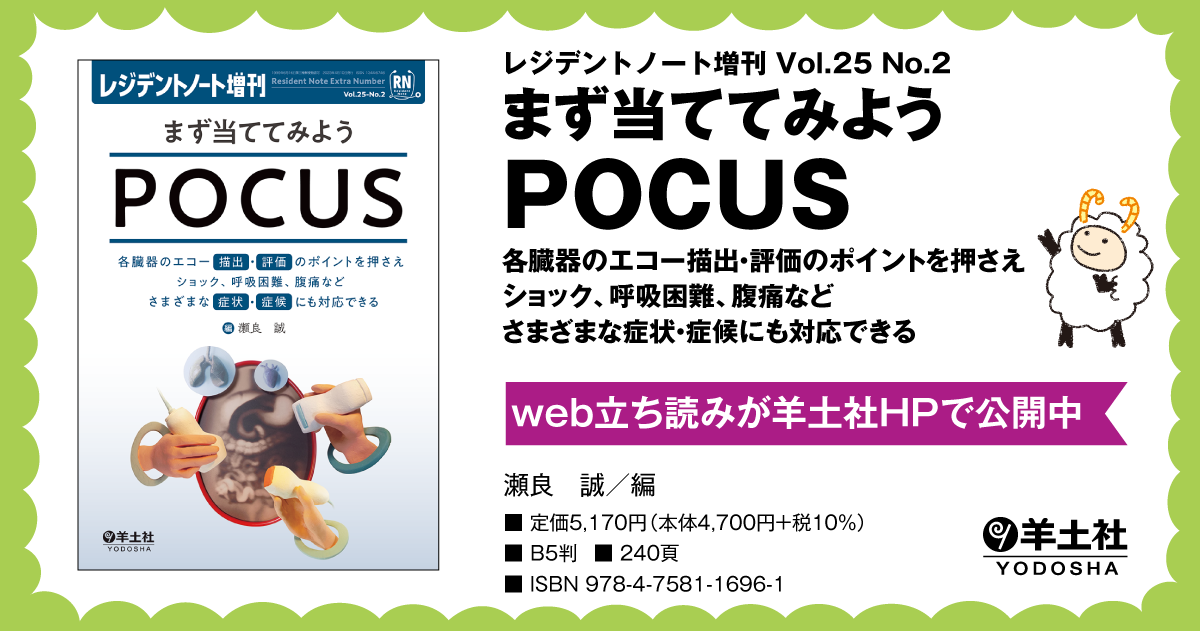

レジデントノート増刊 Vol.25 No.2 まず当ててみようPOCUS〜各

レジデントノート増刊Vol.25No.2まず当ててみようPOCUS?各臓器のエコー描出・評価のポイントを押さえショック、呼吸困難、腹痛などさまざまな症状・症候にも対応できる

羊土社

瀬良誠

レジデントノート増刊Vol.25No.2まず当ててみようPOCUS?各臓器のエコー描出・評価のポイントを押さえショック、呼吸困難、腹痛などさまざまな症状・症候にも対応できる

羊土社

瀬良誠